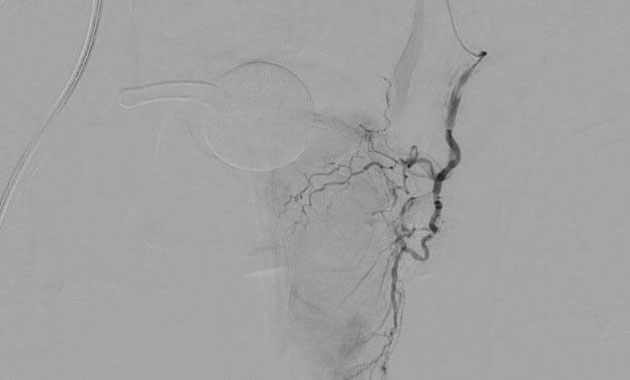

Prostate artery embolization (PAE) is a minimally invasive alternative to surgical procedures like TURP. PAE shrinks the prostate by treating its blood vessels. It is performed by an interventional radiologist through a small incision in the upper thigh.

Dr. Ryan Kohlbrenner and his team use specialized techniques to perform prostate artery embolization (PAE), a procedure being increasingly used in the United States to treat prostate gland enlargement and its associated urinary symptoms. Through a small incision in the upper thigh, access to the prostate's blood vessels is gained, and small particles are injected to slow the blood flow to the gland. In the weeks and months following PAE, the prostate relaxes and shrinks, resulting in symptom relief for most men. Although conventional prostate surgery can be associated with complications like impotence and incontinence, PAE is a minimally-invasive alternative that is not known to cause these issues. We are happy to now offer this procedure to UCSF patients.